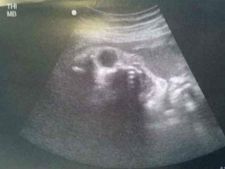

ಭಯ ಹುಟ್ಟಿಸುವ ಆ ಅಲ್ಟ್ರಾಸೌಂಡ್ ಸ್ಕ್ಯಾನ್ ಚಿತ್ರಗಳು!!